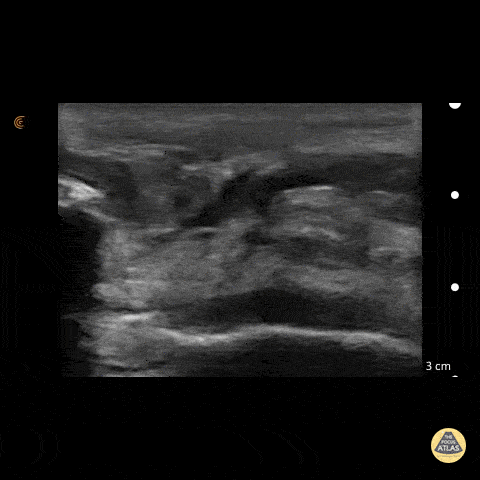

50 y/o M presents with acute left anterior knee pain after fall. On exam, patient noted to have high riding patella. Longitudinal sonogram of the infrapatellar region showed marked discontinuity of the normally hyperechoic linear patterned tendon. The discontinuity is replaced with an anechoic collection indicative of hemorrhage. Comparison to normal knee can be seen on the next post. Of note, anisotropy may be encountered when utilizing ultrasound, leading to artifact. Depending on the angle of the insonating beam, a normally hyperechoic structure may be falsely viewed as hypoechoic due to poor return of echo. Ensure US probe remains perpendicular to the tendon to minimize this artifact. Dr. Hannah Moreira, Dr. Tareq Azad, Dr. Kyle Kelson - Kings County/SUNY Downstate Emergency Medicine